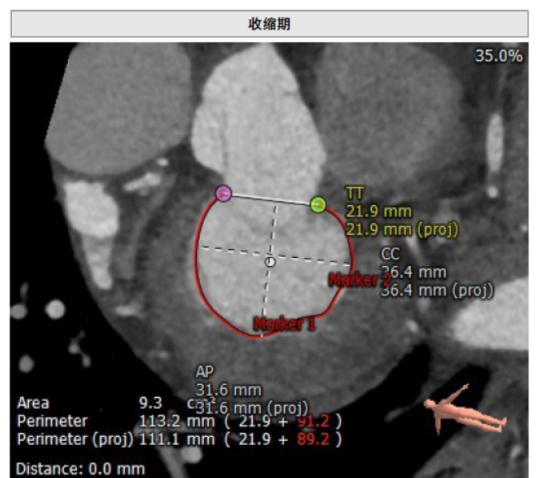

术前CT:瓣环直径